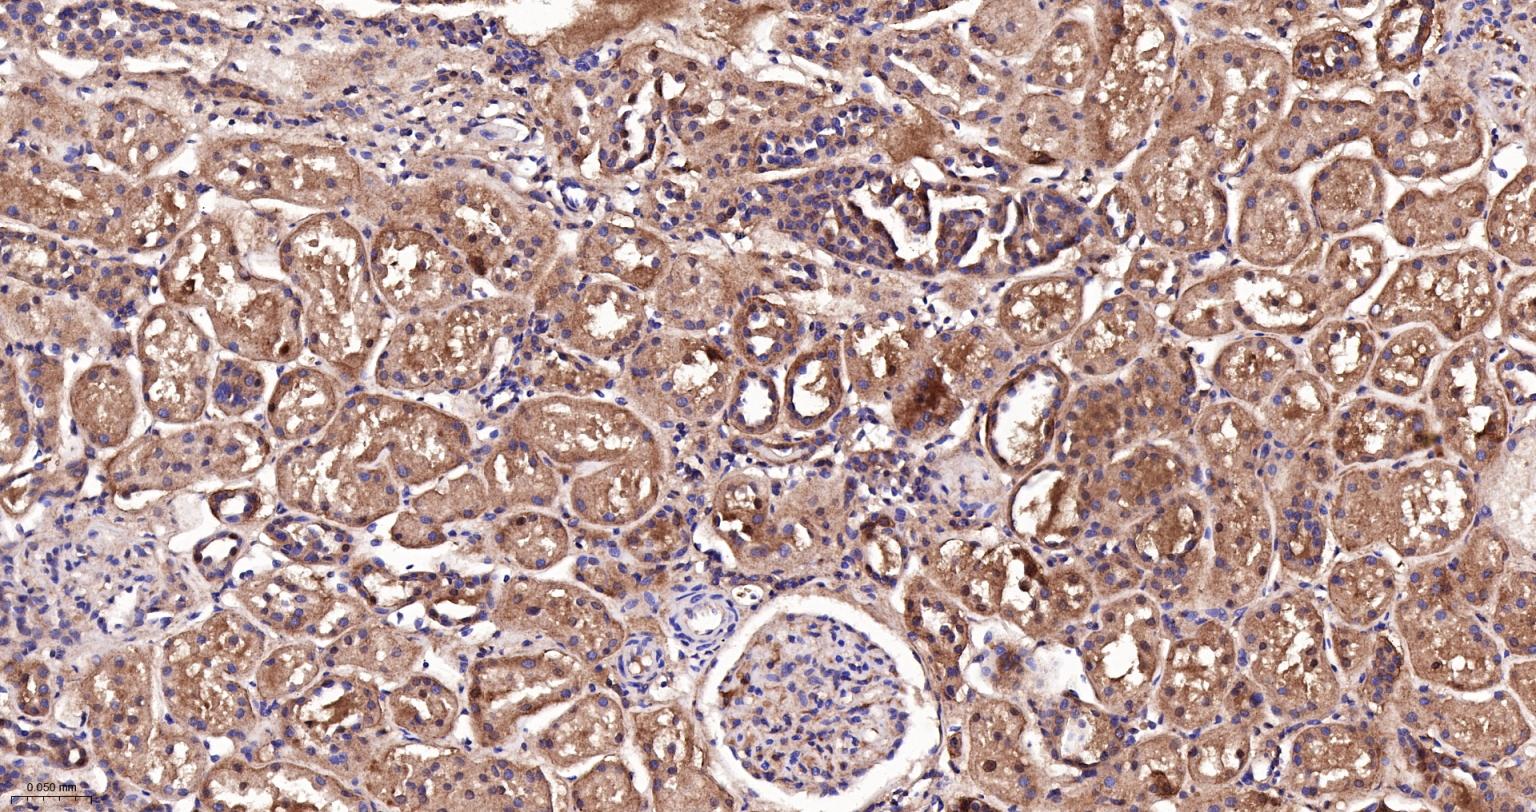

Paraformaldehyde-fixed, paraffin embedded Human Kidney; Antigen retrieval by boiling in sodium citrate buffer (pH6.0) for 15 min; The section was incubated with DDAH1 Monoclonal Antibody, Unconjugated (bsm-61706R) at 1:200 overnight at 4°C, followed by conjugation to the bs-0295G-HRP and DAB (C-0010) staining.